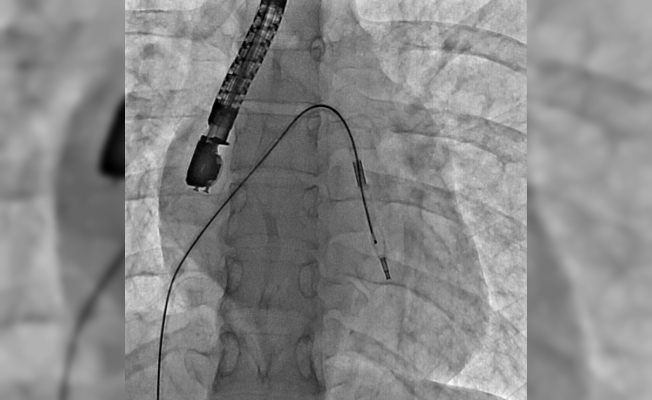

Eskişehir Şehir Hastanesi’nde ilk defa mitral balon operasyonu yapıldı. Operasyon, anjiyografi cihazı ile adım adım kaydedildi.

Eskişehir Şehir Hastanesi’nde Kardiyoloji Uzmanı Dr. Mehmet Özgeyik ve 4 kişilik ekibi tarafından ilk defa mitral balon operasyonu yapıldı. Türkiye’de az sayıda yapılan kalp kapağı balon işlemiyle yeni anne olmuş genç bir hasta sağlığına kavuştu. Bu sayede hastalar ameliyat olmaktan, ömür boyu kan sulandırıcı ilaçlar kullanmaktan ve metal bir kalp kapağı ile yaşamaktan kurtuluyor.

Gerçekleşen başarılı operasyon hakkında konuşan Kardiyoloji Uzmanı Dr. Mehmet Özgeyik, "Bu işlemi genellikle kalp kapaklarında ciddi darlık olan genç hastaların kişilere uyguluyoruz. Buradaki amacımız ameliyat olmadan, kasıktan küçük iki damar yolu açarak hastalarımızın kapak darlıklarını uzun süreli olarak genişletmeyi hedefliyoruz. Burada 23 yaşında yeni anne olmuş genç bir hastamıza müdahale yaptık. Hastamız ya kapak ameliyatı olacaktı ya da bu işlem sayesinde kapak darlığını aşmayı planlıyorduk. İşlem gayet başarılı oldu. Hastamızın kapak darlığını genişlettik. En azından 10-15 sene boyunca ameliyata gerek kalmadan hastamızı ilaç tedavisiyle takip etmeyi planlıyoruz" diye konuştu.

"Hastanın kendi kalp kapağını kullanmasını sağlamış olduk"

Cerrahi operasyonlar yerine mitral balon işlemiyle hastaları sağlıklarına kavuşturmak istediklerini aktaran Dr. Özgeyik, "Hastanemizde ilk kez yapılan bir işlem. Bu işlem için uygun hasta bulmak biraz zor oluyor çünkü çok sık yapılan bir işlem değil. Fakat gelecekte hasta portföyümüzün de artması ile birlikte daha sık yapmayı planlıyoruz. En azından hastalarımızı büyük bir cerrahi operasyona vermeden böyle küçük işlemlerle hayat kalitelerini artırmayı planlıyoruz. Hastamız ameliyata gitmiş olsaydı büyük bir operasyon geçirmiş olacaktı. Göğüs bölgesinde büyük bir kesiğe maruz kalacaktı. Aynı zamanda ömür boyu kullanması gereken farklı ilaçlar olacaktı. Hasta kendisine ait olmayan metal bir kapakla yaşamak zorunda kalacaktı. Biz bu işlemde hastaya kasıktan iki tane damar yolu açtık. Hastaya neşter ile kesme işlemi uygulamaktan kurtardık. Ayrıca hastanın hayatı boyunca kullanacağı kan sulandırıcı ilaçları uzunca bir süre ertelemiş olduk. En önemlisi de hastanın kendi kalp kapağını kullanmasını sağlamış olduk ve metal kapak yükünden kurtulmuş oldu" şeklinde konuştu.